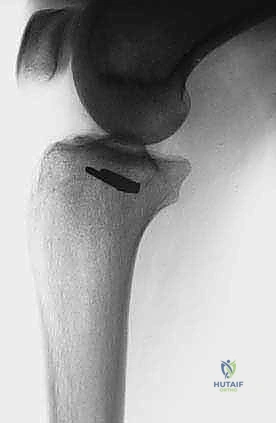

- الأشعة السينية (X-rays): الخطوة الأولى. تظهر التغيرات في الهيكل العظمي، تآكل العظم، أو التفاعلات السمحاقية (Periosteal reaction) التي تدل على وجود ورم.

- التصوير المقطعي المحوسب (CT Scan): ممتاز لتقييم التفاصيل الدقيقة للقشرة العظمية واكتشاف أي تكلسات داخل الورم.

5. الاستئصال العظمي بهوامش آمنة (Osteotomy with Wide Margins)

يتم تحديد نقاط القطع على العظم أعلى وأسفل الورم بمسافة آمنة (عادة 2-3 سم من الأنسجة السليمة لضمان عدم ترك أي خلايا سرطانية). يتم استخدام مناشير عظمية دقيقة لقطع الشظية. يتم استخراج الكتلة الورمية كقطعة واحدة (En bloc) مع العضلات المحيطة بها الملتصقة بالورم.

- إذا كان الاستئصال في أسفل الشظية (الكعب الوحشي): هنا يكمن التحدي الأكبر. يجب إعادة بناء مفصل الكاحل لضمان قدرة المريض على المشي. قد يتضمن ذلك نقل عظم آخر، أو استخدام طعوم عظمية، أو إجراء دمج لمفصل الكاحل (Arthrodesis) باستخدام شرائح ومسامير معدنية متطورة.